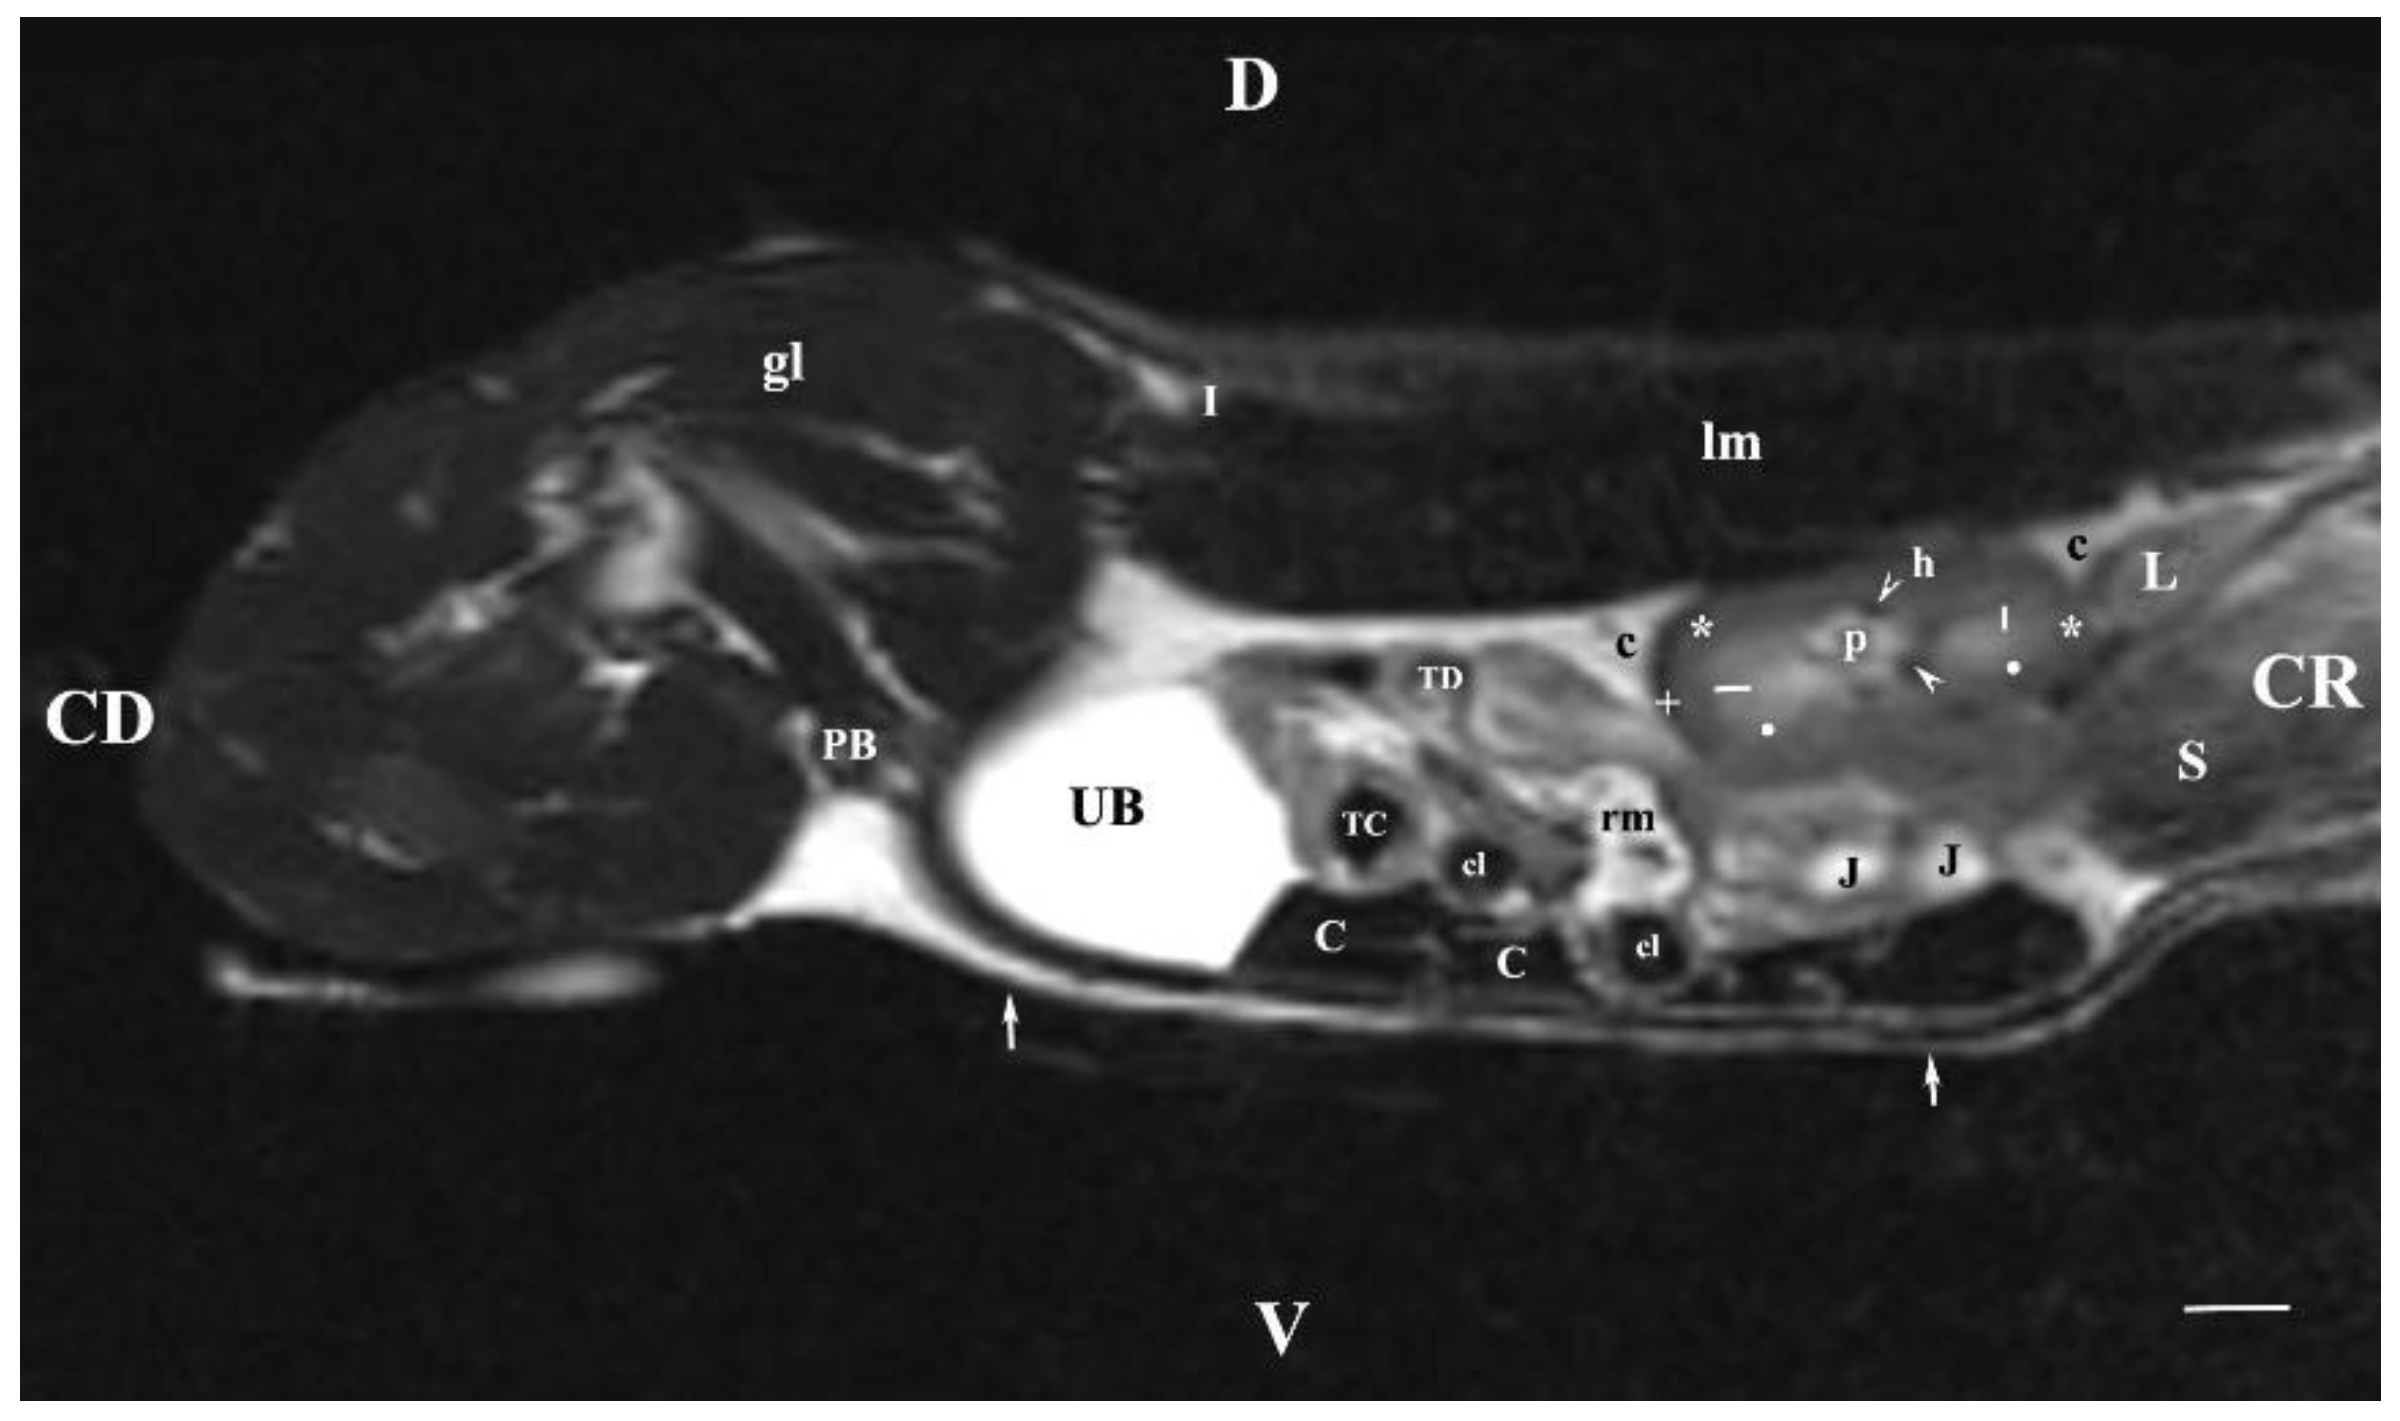

Sagittal T2-weighted image of the abdominal cavity 30 mm to the right of the median plane showed the almost entire right kidney (in the dorsal lumbar area) and the right ureter and the urinary bladder as well. The right kidney demonstrated its specific bean shape, and the renal hilus was seen as a hypo intense dorsomedially located structure. The renal pelvis was clearly outlined as a hyper intense finding of irregular borders. Peripherally to it, the hypo intense dorsal and ventral recesses were visualized. The corticomedullary definition was clearly demarcated as an intense irregular finding of transient intensity, situated between the hyper intense medulla and the relatively hypo intense cortex. The renal adipose capsule was hyper intense and the fibrous capsule—hypo intense. The craniolateral border of the right kidney touched the heterogeneous hypo signal liver. The inner and outer areas of the kidney medulla were not distinguished. Caudoventrally to the hyper intense adipose capsule of the right kidney appeared the hyper intense tubular right ureter whose lumen was more intense than its walls. The hyper intense signal of the urinary bladder body was observed in the caudal abdomen, clearly delineated from the adjacent soft tissues. The latter comprised the heterogeneous images with varying signal intensity of the transverse colon, the transverse duodenum, the caecum, the jejunum and the mesentery. The urinary bladder neck was not observed (Figure 7).

Figure 7. MRI imaging anatomy of organs from the middle abdominal region (sagittal section) (T2-weighted sequence 30 mm to the right of the median plane) (Right kidney). CD-caudal, CC-cranial, D-dorsal, V-ventral. (UB) urinary bladder; (p) renal pelvis; (black star) renal cortex; (white line) renal medulla; (black point) corticomedullary junction; (h) renal hilus; (white cross) fibrous capsule; (oblique white arrowhead) dorsal and ventral renal recess; (perpendicular black arrowhead) ureter; (S) stomach; (L) liver; (c) renal adipose capsule; (rm) mesenterial root; (J) jejunum; (TD) transverse duodenum; (TC) transverse colon; (C) caecum; (A) adipose tissue; (PB) pubic bone; (lm) longissimus muscle; (gm) gluteal muscles; (I) ilium (white perpendicular arrow) abdominal wall. Line=10mm.

The sagittal T2-weighted MRI (30 mm lateral and right to the median plane) demonstrated only the image of the right kidney, due to the relatively close location of the right kidney to the median plane compared to that of the left kidney, which remained more aside. The image of the right kidney was completely defined and informative, and its different parts showed a various degree of heterogeneity and intensity. The image of the right ureter was caudal to the caudal end of the right kidney, with hyper intense signal characteristics without clear distinction between the lumen and the ureteral walls. Therefore, the right ureter was not filled with urine at the time of MR scanning due to the caudal tissue motility wave that moved urine towards the urinary bladder. The difference in the intensity of the renal image (hypo intense) and the renal pelvis image (hyper intense) was due to the option of T2-weighted sequence—indicating fluid findings. The lack of urine in the renal sinus was the cause for the hypo intense signal. Compared to the transverse section, the different parts of the medulla on the sagittal one had no defined signal intensity. The renal cortex demonstrated a lower relative intensity with respect to the medulla on the sagittal section than on the transverse one. The homogeneous character of tissue intensity of the cortex was due to the difficult differentiation of its granulosa part. Opposing to the cortex, the medulla was heterogeneous and hyper intense because of the unclear distinction of its two areas and the increased degree of hydration. The kidney fibrous capsule and the renal sinus were the structures with the lowest image intensity, consequently to their low fluid content.

The hyper intense and homogeneous T2-weighted image of the urinary bladder lumen was detected in the caudal abdomen; the bladder flexion to the left was not observed due to the sagittal imaging method.